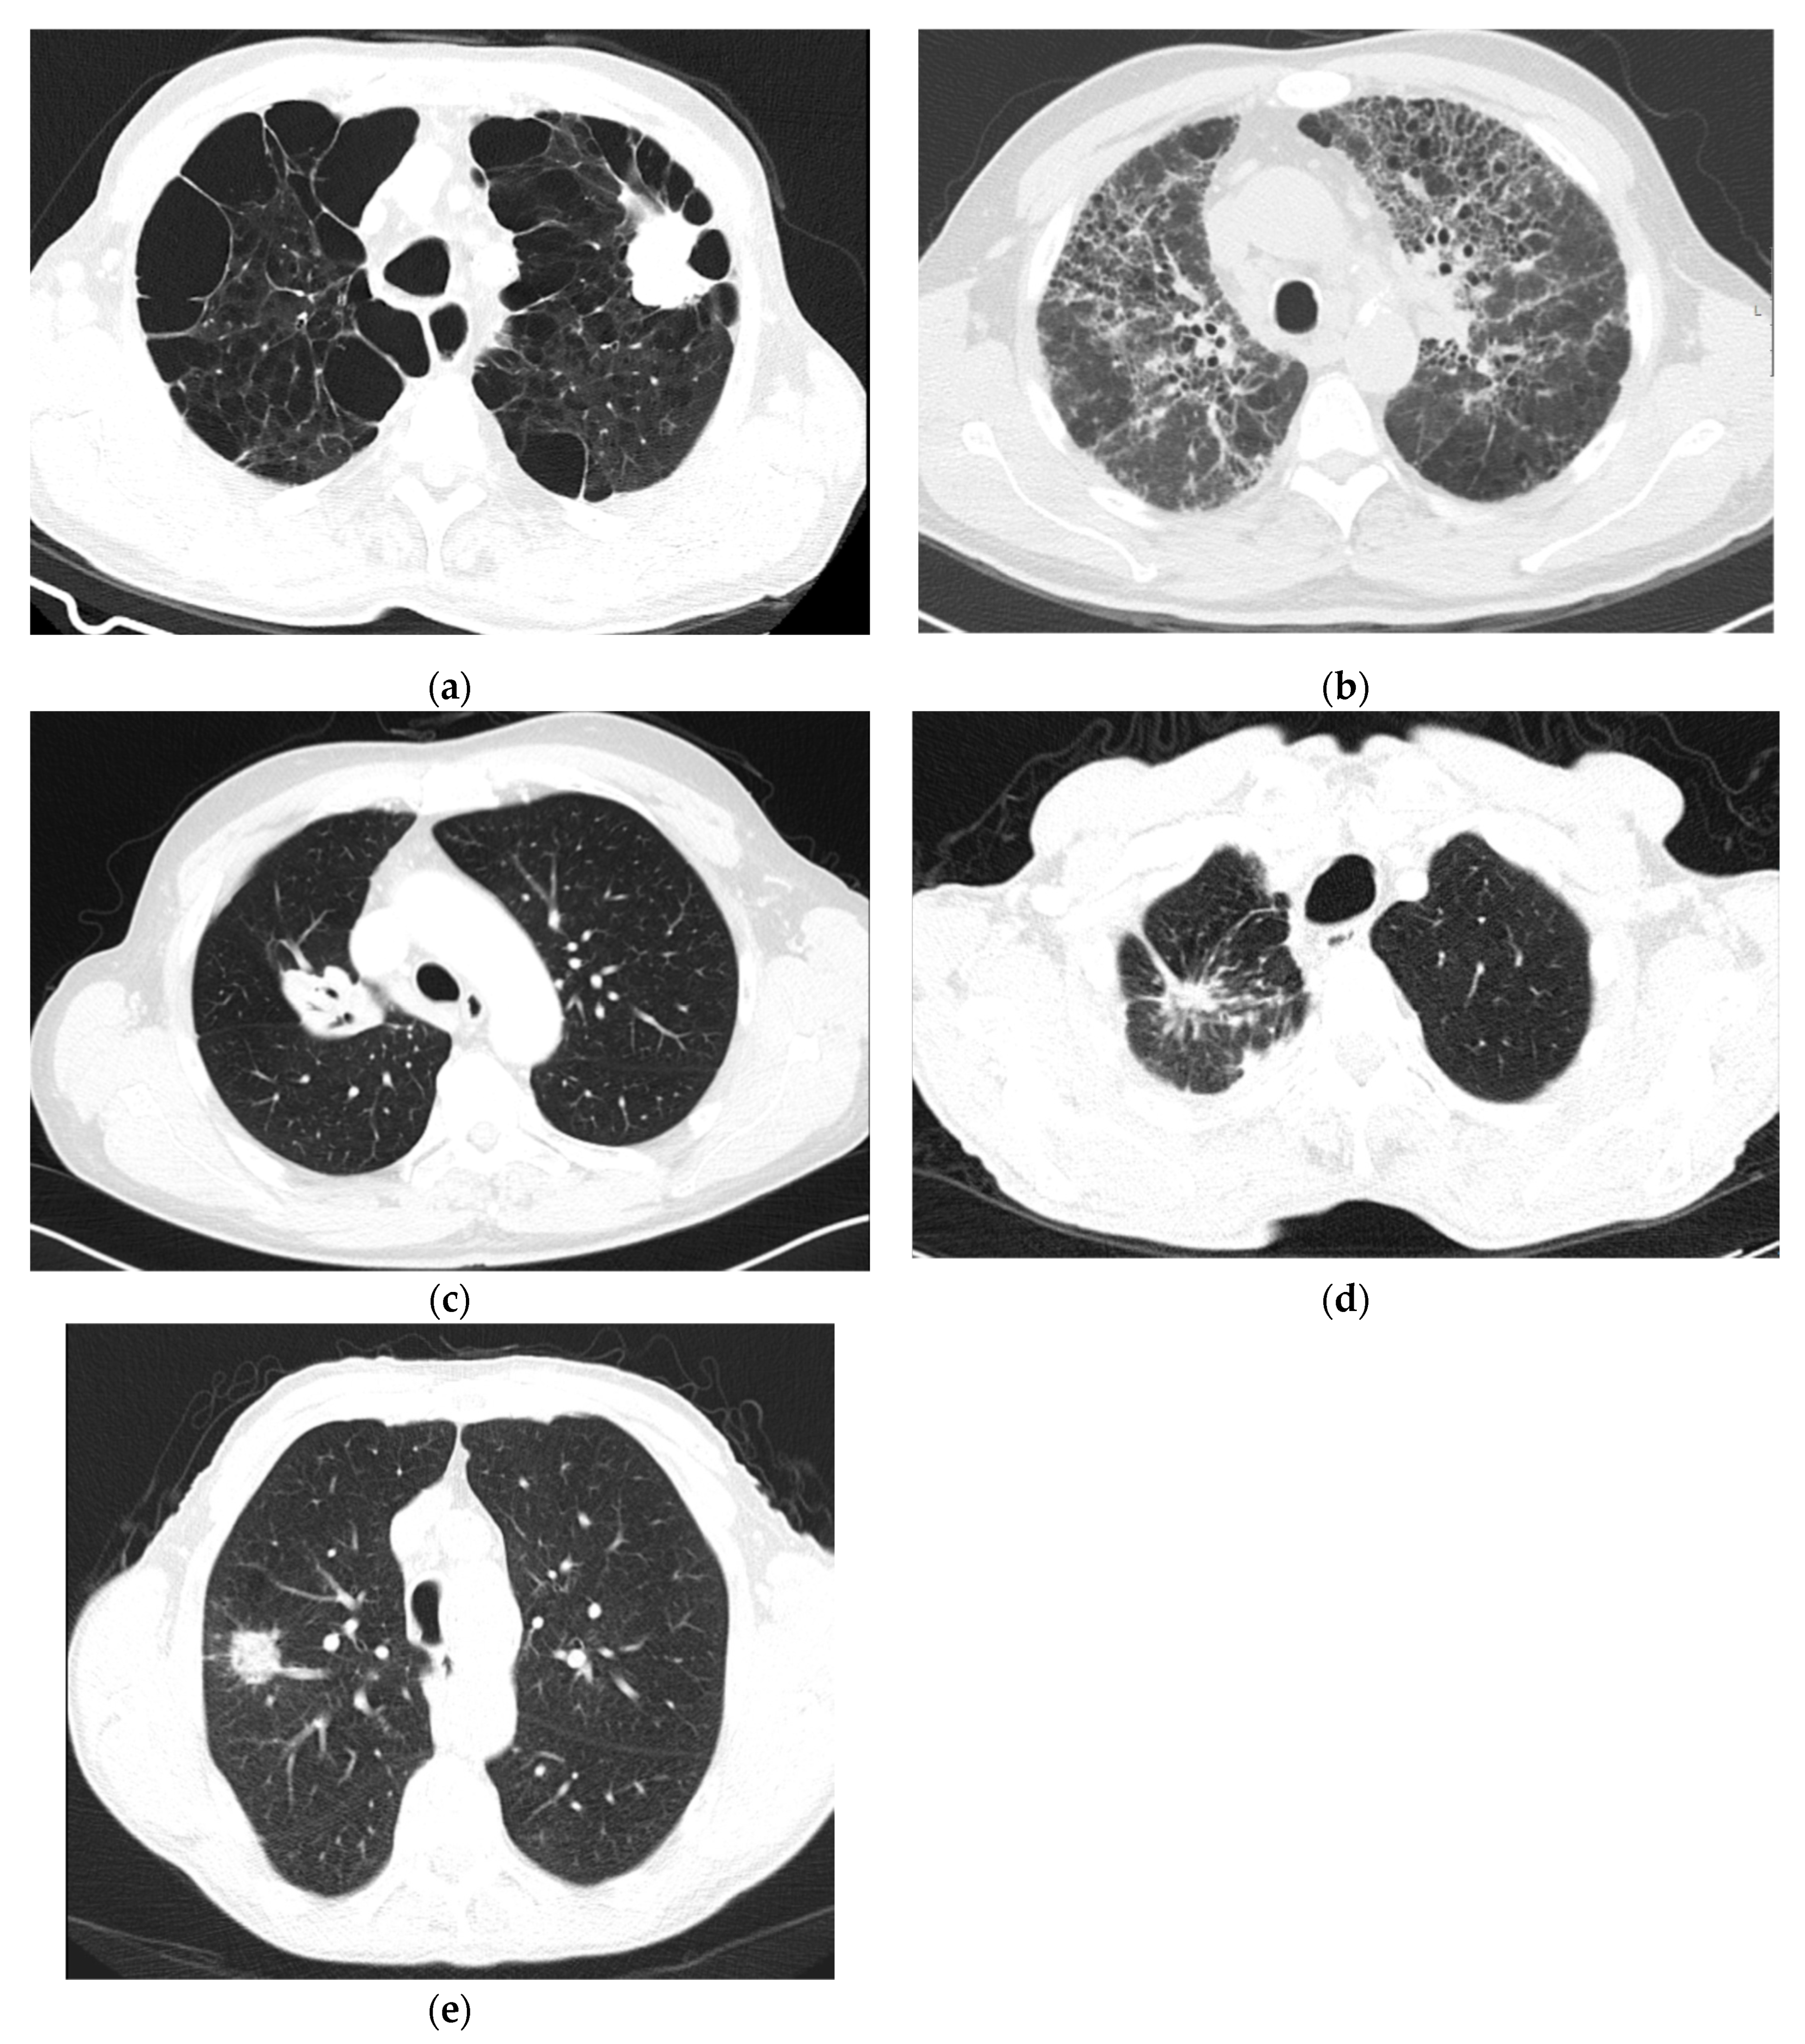

- Hansell, D.; Bankier, A.A.; MacMahon, H.; McLoud, T.C.; Müller, N.L.; Remy, J. Fleischner Society: Glossary of terms for thoracic imaging. Radiology 2008, 246, 697–722. [Google Scholar] [CrossRef]

- Raju, S.; Ghosh, S.; Mehta, A.C. Chest CT signs in pulmonary disease: A pictorial review. Chest 2017, 151, 1356–1374. [Google Scholar] [CrossRef] [PubMed]

- Xiang, W.; Xing, Y.; Jiang, S.; Chen, G.; Mao, H.; Labh, K.; Jia, X.; Sun, X. Morphological factors differentiating between early lung adenocarcinomas appearing as pure ground-glass nodules measuring ≤10 mm on thin-section computed tomography. Cancer Imaging 2014, 14, 33. [Google Scholar] [CrossRef]

- Qiang, J.; Zhou, K.; Lu, G.; Wang, Q.; Ye, X.; Xu, S.; Tan, L. The relationship between solitary pulmonary nodules and bronchi: Multi-slice CT–pathological correlation. Clin. Radiol. 2004, 59, 1121–1127. [Google Scholar] [CrossRef] [PubMed]

- Snoeckx, A.; Reyntiens, P.; Desbuquoit, D.; Spinhoven, M.J.; Van Schil, P.E.; Van Meerbeeck, J.P.; Parizel, P.M. Evaluation of the solitary pulmonary nodule: Size matters, but do not ignore the power of morphology. Insights Imaging 2018, 9, 73–86. [Google Scholar] [CrossRef]

- Chu, Z.-G.; Zhang, Y.; Li, W.-J.; Li, Q.; Zheng, Y.-N.; Lv, F.-J. Primary solid lung cancerous nodules with different sizes: Computed tomography features and their variations. BMC Cancer 2019, 19. [Google Scholar] [CrossRef]

- Hu, H.; Wang, Q.; Tang, H.; Xiong, L.; Lin, Q. Multi-slice computed tomography characteristics of solitary pulmonary ground-glass nodules: Differences between malignant and benign. Thorac. Cancer 2016, 7, 80–87. [Google Scholar] [CrossRef] [PubMed]

- Yang, J.; Wang, H.; Geng, C.; Dai, Y.; Ji, J. Advances in intelligent diagnosis methods for pulmonary ground-glass opacity nodules. Biomed. Eng. Online 2018, 17, 20. [Google Scholar] [CrossRef] [PubMed]